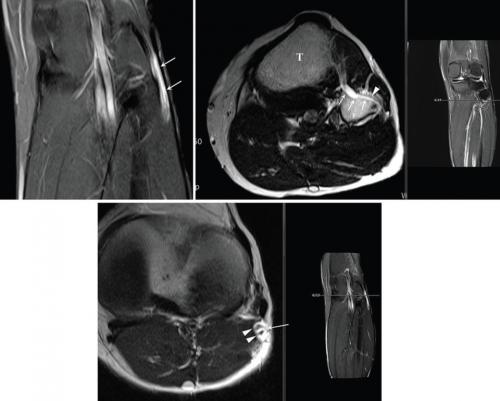

Ç㸮¿¡¼­ ½ÃÀÛÇÏ¿© ¾ûµ¢ÀÌ µÚÂÊÀ» Áö³ª ´Ù¸® µÚÆí Çã¹÷Áö, Á¾¾Æ¸®¸¦ µû¶ó ¹ß±îÁö ³»·Á°¡´Â ¿ì¸® ¸ö¿¡¼­ °¡Àå Å©°í ±½Àº ½Å°æ ´Ù¹ßÀÎ Á°ñ½Å°æ¿¡¼­ ¹ß»ýÇÑ Èñ±Í ³­Ä¡¼º ¾ç¼ºÁ¾¾ç '½Å°æ³» °áÀýÁ¾'(È­»ìÇ¥ ºÎºÐ) MRI ¿µ»ó °Ë»ç »çÁø.